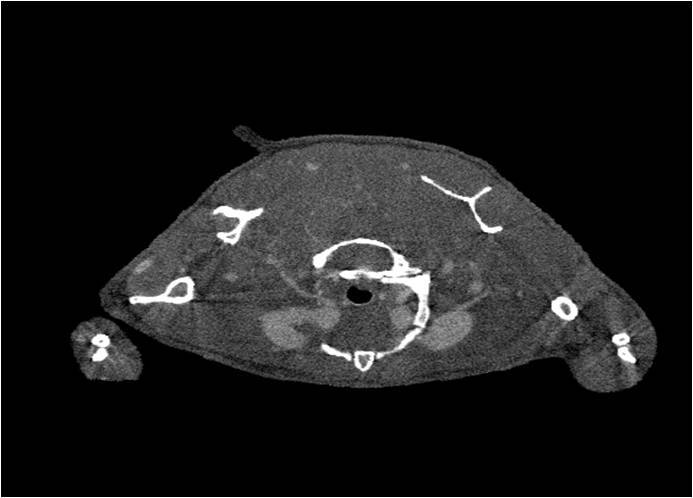

肺轉(zhuǎn)移

小鼠模式,22.5μm像素

正常

8天 14天

無造影劑注入 造影劑注入